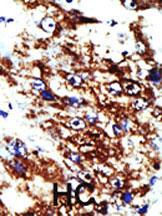

Formalin-fixed and paraffin-embedded human cancer tissue reacted with the primary antibody, which was peroxidase-conjugated to the secondary antibody, followed by DAB staining. This data demonstrates the use of this antibody for immunohistochemistry; clinical relevance has not been evaluated. BC = breast carcinoma; HC = hepatocarcinoma.